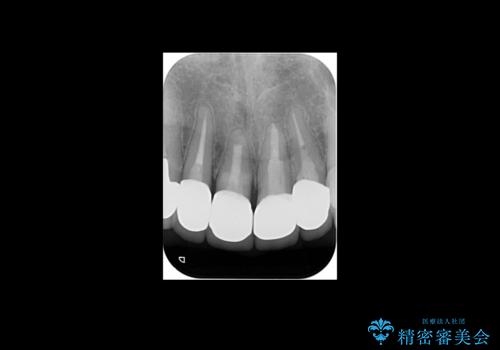

- 他の部位の治療で来院されていましたが、30年以上前に行った前歯のかぶせ物のきわがあっておらず虫歯になってきていました。

神経の治療から念のためやり直ししてからセラミックでかぶせました。

金属の土台が入っていましたがすべて外し、ファイバーコアでやり替えています。